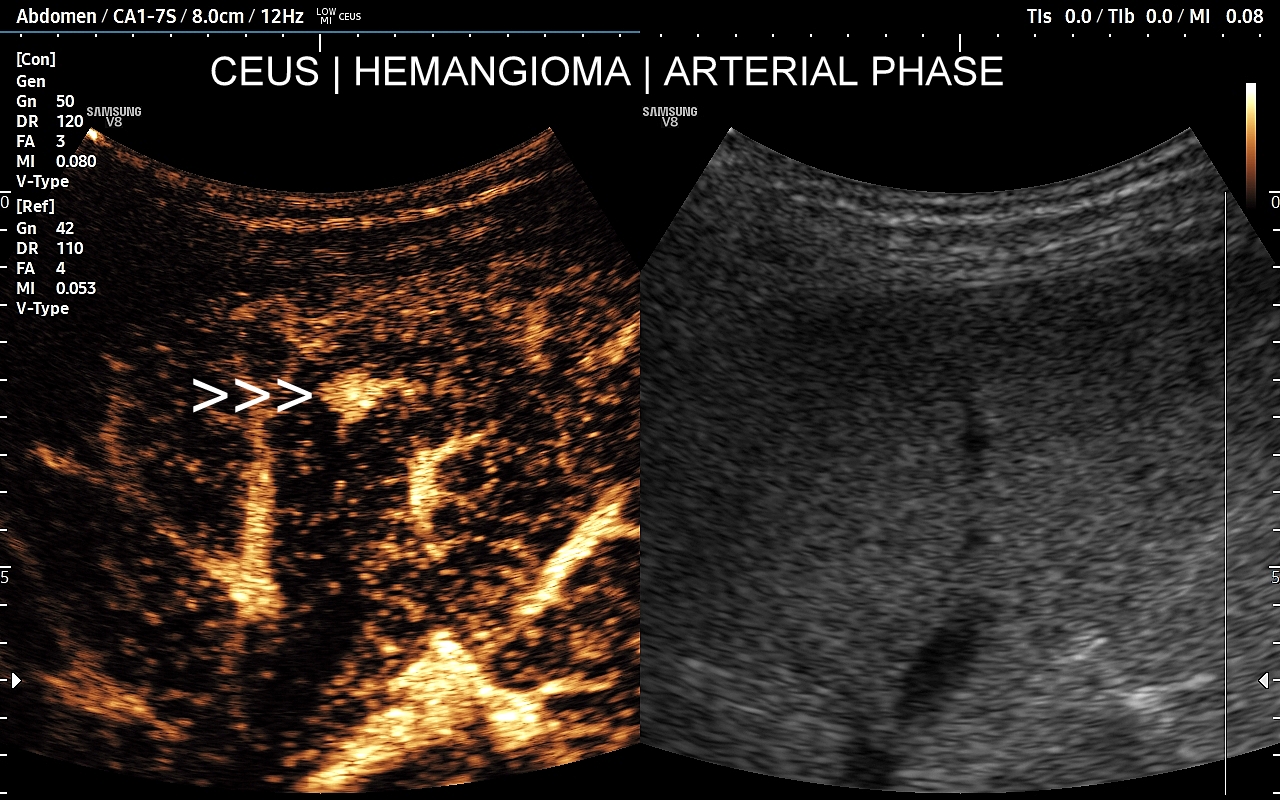

Najbardziej charakterystyczną cechą naczyniaka wątroby w badaniu CEUS jest jego wypełnianie w postaci guzkowej (ang. peripheral nodular enhancement) od obwodu ku centrum zmiany (ang. centripetal). Szybkość wypełniania bywa różnorodna, może być powolna lub szybka. W przypadku szybkiego wypełniania (tzw. flash-filling), w celu wykazania charakterystycznego centrypetalnego wypełniania niezbędna może być postprocessing’owa analiza poklatkowa zapisanego nagrania badania. W fazie późnej naczyniak wątroby pozostaje izowzmocniony lub hyperwzmocniony w stosunku do natywnego miąższu wątroby.

W przypadku dużych naczyniaków obszary, które uległy wykrzepianiu pozostają awaskularne przez wszystkie fazy badania CEUS, tj. nie wypełniają się kontrastem (nonenhancing). W przeciwieństwie do powyższego konstelacja, w której to w fazie wczesnej pojawia się wzmocnienie, a następnie w fazie wrotnej lub późnej ulega wypłukaniu (hypoenhancement) świadczy o cechach złośliwych diagnozowanej zmiany ogniskowej w wątrobie i wyklucza rozpoznanie naczyniaka.